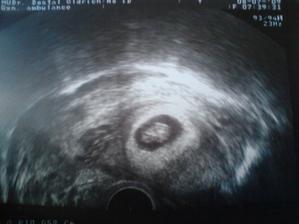

.........8.7.09 kontrola dopadla dobře jsme 7 tt a už začíná srdeční akce ,cysta jse zmenšuje, další kontrola nás čeká za měsíc 5.8.2009.ještě nás mezi kontrolou u gyndaře čeká genetické vyšetření v I trimestru 22.7 máme jed na krev.......22.7.09 jsme byly v olomouci na krvi a UTZ nás čeká 13.8.09 už se na něho těším,ale i když mám strach aby vše bylo v pořádku..........5.8.09poradna dopadla skvěle už jsme zase povyrostly a mimišek se furt vrtěl a mával ručička a kopal nožičkama byl to nádherný pocit 🙂 už jsme dostaly i průkazku další kontrola za měsíc ..........7.9.09+odběr krve